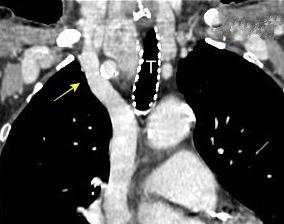

Triada de Garland

Ganglios paratraqueales derechos e hiliares bilaterales

95% de pacientes tienen ganglios hiliares bilaterales aislados o con afectación mediastínica (espec. paratraqueal derecho).

Criado E et al. Pulmonary sarcoidosis: typical and atypical manifestations at high-resolution CT with pathologic correlation. Radiographics. 2010